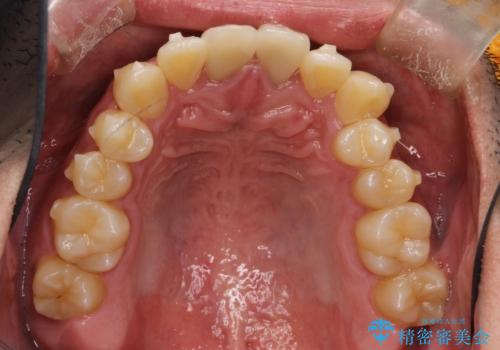

- 前歯のガタガタを主訴に来院されました。

上下の前歯のガタガタと左上の歯が反対にかんでいる状態でした。

上下の歯と歯の間をわずかに削り並べる計画としました。

目立たずに歯並びがよくなり、前歯に装着されたセラミックも壊さずに矯正治療が終了し満足していただけました。